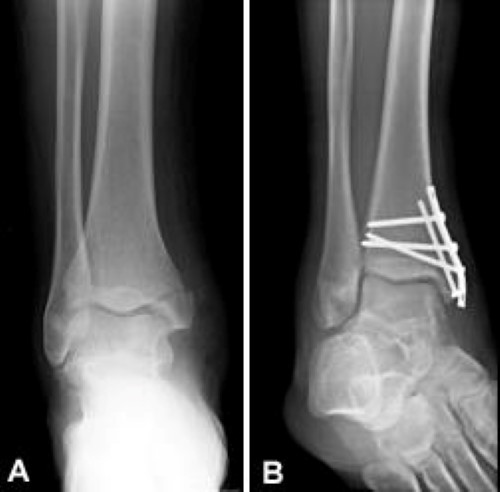

Trimalleolar Right Ankle Fracture Ankle Fracture Ankle Surgery Medical

Malleolus — a rounded bony prominence such as those on either side of the ankle joint. Ankle fractures are among the most common fractures in adults, and the medial malleolus is often involved. Approach to the lateral malleolus. Related online courses on physioplus. Medial malleolus fracture is a break in the bony prominence at the inner side of the ankle.

Изображение ankle anatomy medial malleolus. That term is however too technical to be used in the story i'm writing. Approach to the lateral malleolus. Surgery on the medial malleoli can improve the chances of successful sometimes, a medial malleolus fracture may result in impaction of the ankle joint, which is when. Ankle fractures are among the most common fractures in adults, and the medial malleolus is often involved. Image showing the lateral malleolus as part of the fibula. The posterior malleolus, felt on the back of your ankle is also part of the tibia's base. Of the foot and lowermost portion of the leg, which contain this skeletal joint while malleolus is the bony prominence on each side of the ankle joint.